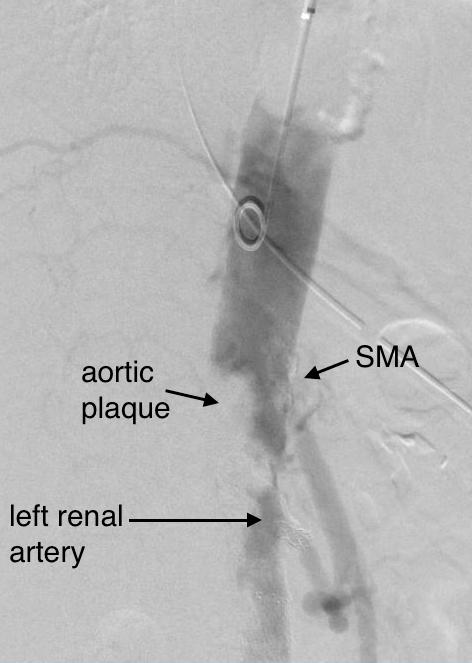

The patient is a middle aged man in his 50’s who presented with a type B aortic dissection. His dissection flap spanned from his left subclavian artery to the infrarenal aorta. He was a long time smoker and had hypertension that was difficult to control, made much worse after his dissection. He had a moderate dilatation of his thoracic aorta, maximally 36mm and tapering to 35mm in visceral segment. There was a 4.9cm infrarenal AAA where the dissection terminated.

His chest pain resolved with blood pressure control and he was discharged, but in followup his thoracic aortic segment grew and his blood pressure worsened, never getting below a 150mmHg systolic despite multiple agents. CTA two months after presentation, showed growth of his TAA to 44mm from 36mm in two months and the visceral segment showed that his dissection flap impinged on flow to the right renal artery. His AAA remained the same. He continued to have bouts of chest pain related to hypertension.

The terminus of the stent graft excluded the false lumen in the thoracic aorta but also resulted in filling and pressurization of the false lumen beyond and can be seen as a 44mm lateral dilation of the visceral segment of the aorta which had developed in the 6 month interval since the TEVAR.

The infrarenal neck continued the dissection and had dilated to about 36mm, but was parallel for a good length above the AAA. I decided to treat the inrarenal aorta with direct transabdominal repair. This would allow me to fenestrate the aorta, and possibly prevent further growth of the viseral segment while reserving the retroperitoneum for the visceral segment repair if it came to it. The neck diameter was 36mm.